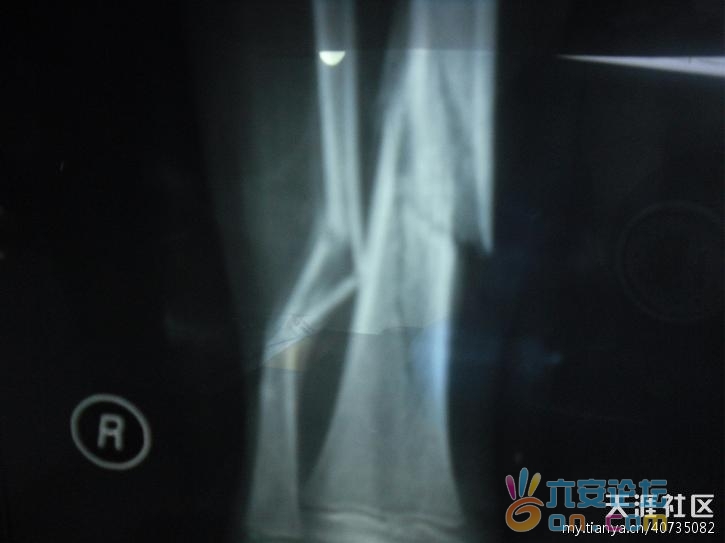

柳江县韦先生向今报反映,其9岁儿子被身为城管工作人员的兼职午托班“老师”教训,腿骨摔断了,经一个多月治疗,至今没有好转迹象。昨日,记者从柳江县公安局拉堡派出所了解到,受伤男童经司法鉴定,为右小腿胫腓骨粉碎性骨折,构成轻伤,伤情符合钝性暴力作用所致。目前,警方对此已立案调查。

经医生诊断,孩子是右侧胫腓骨下段螺旋形粉碎性骨折。为了治好孩子的腿,他们转院到当地一家私人骨科医院。经过10多天稳定下来后,韦向儿子问起当天的情形。儿子说是被“刘老师”高举过头摔在地板上的。

得知孩子是被摔的消息后,韦先生夫妇曾于4月23日到拉堡派出所报案,当时做了笔录,后来又通知孩子去做司法鉴定。昨日上午,记者和韦先生在拉堡派出所看到了司法鉴定书的结论:孩子右小腿胫腓骨粉碎性骨折构成轻伤,伤情符合钝性暴力作用所致。

家长提供的4月1日当天医院拍下的腿部骨折图。

粉碎性骨折图片